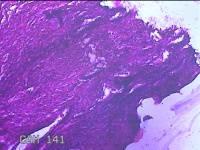

右侧卵巢囊肿

性别

女

年龄

19岁

临床诊断

一般病史

下腹痛1小时。

标本名称

大体所见

灰白暗红色囊壁样组织11x4.5x2.3cm两块,表面糜烂,因已切开,囊内容物已流失,囊壁厚0.1cm。